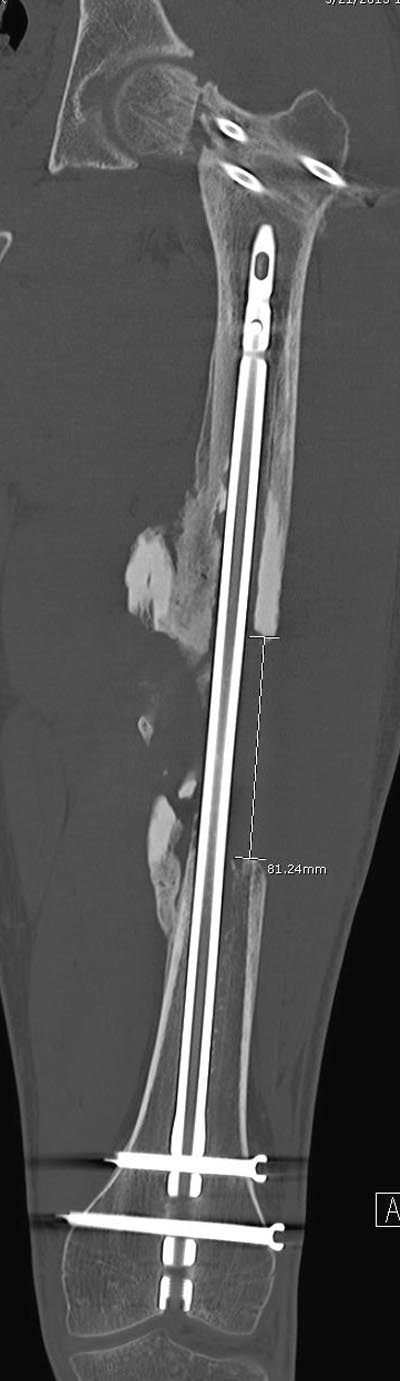

несращения! По истечению 4 месяцев появились признаки варусной

деформации. На СТ срезах несращение шейки и бедра. Риминг, замена на

более толстый гвоздь и вальгусная остеотомия.